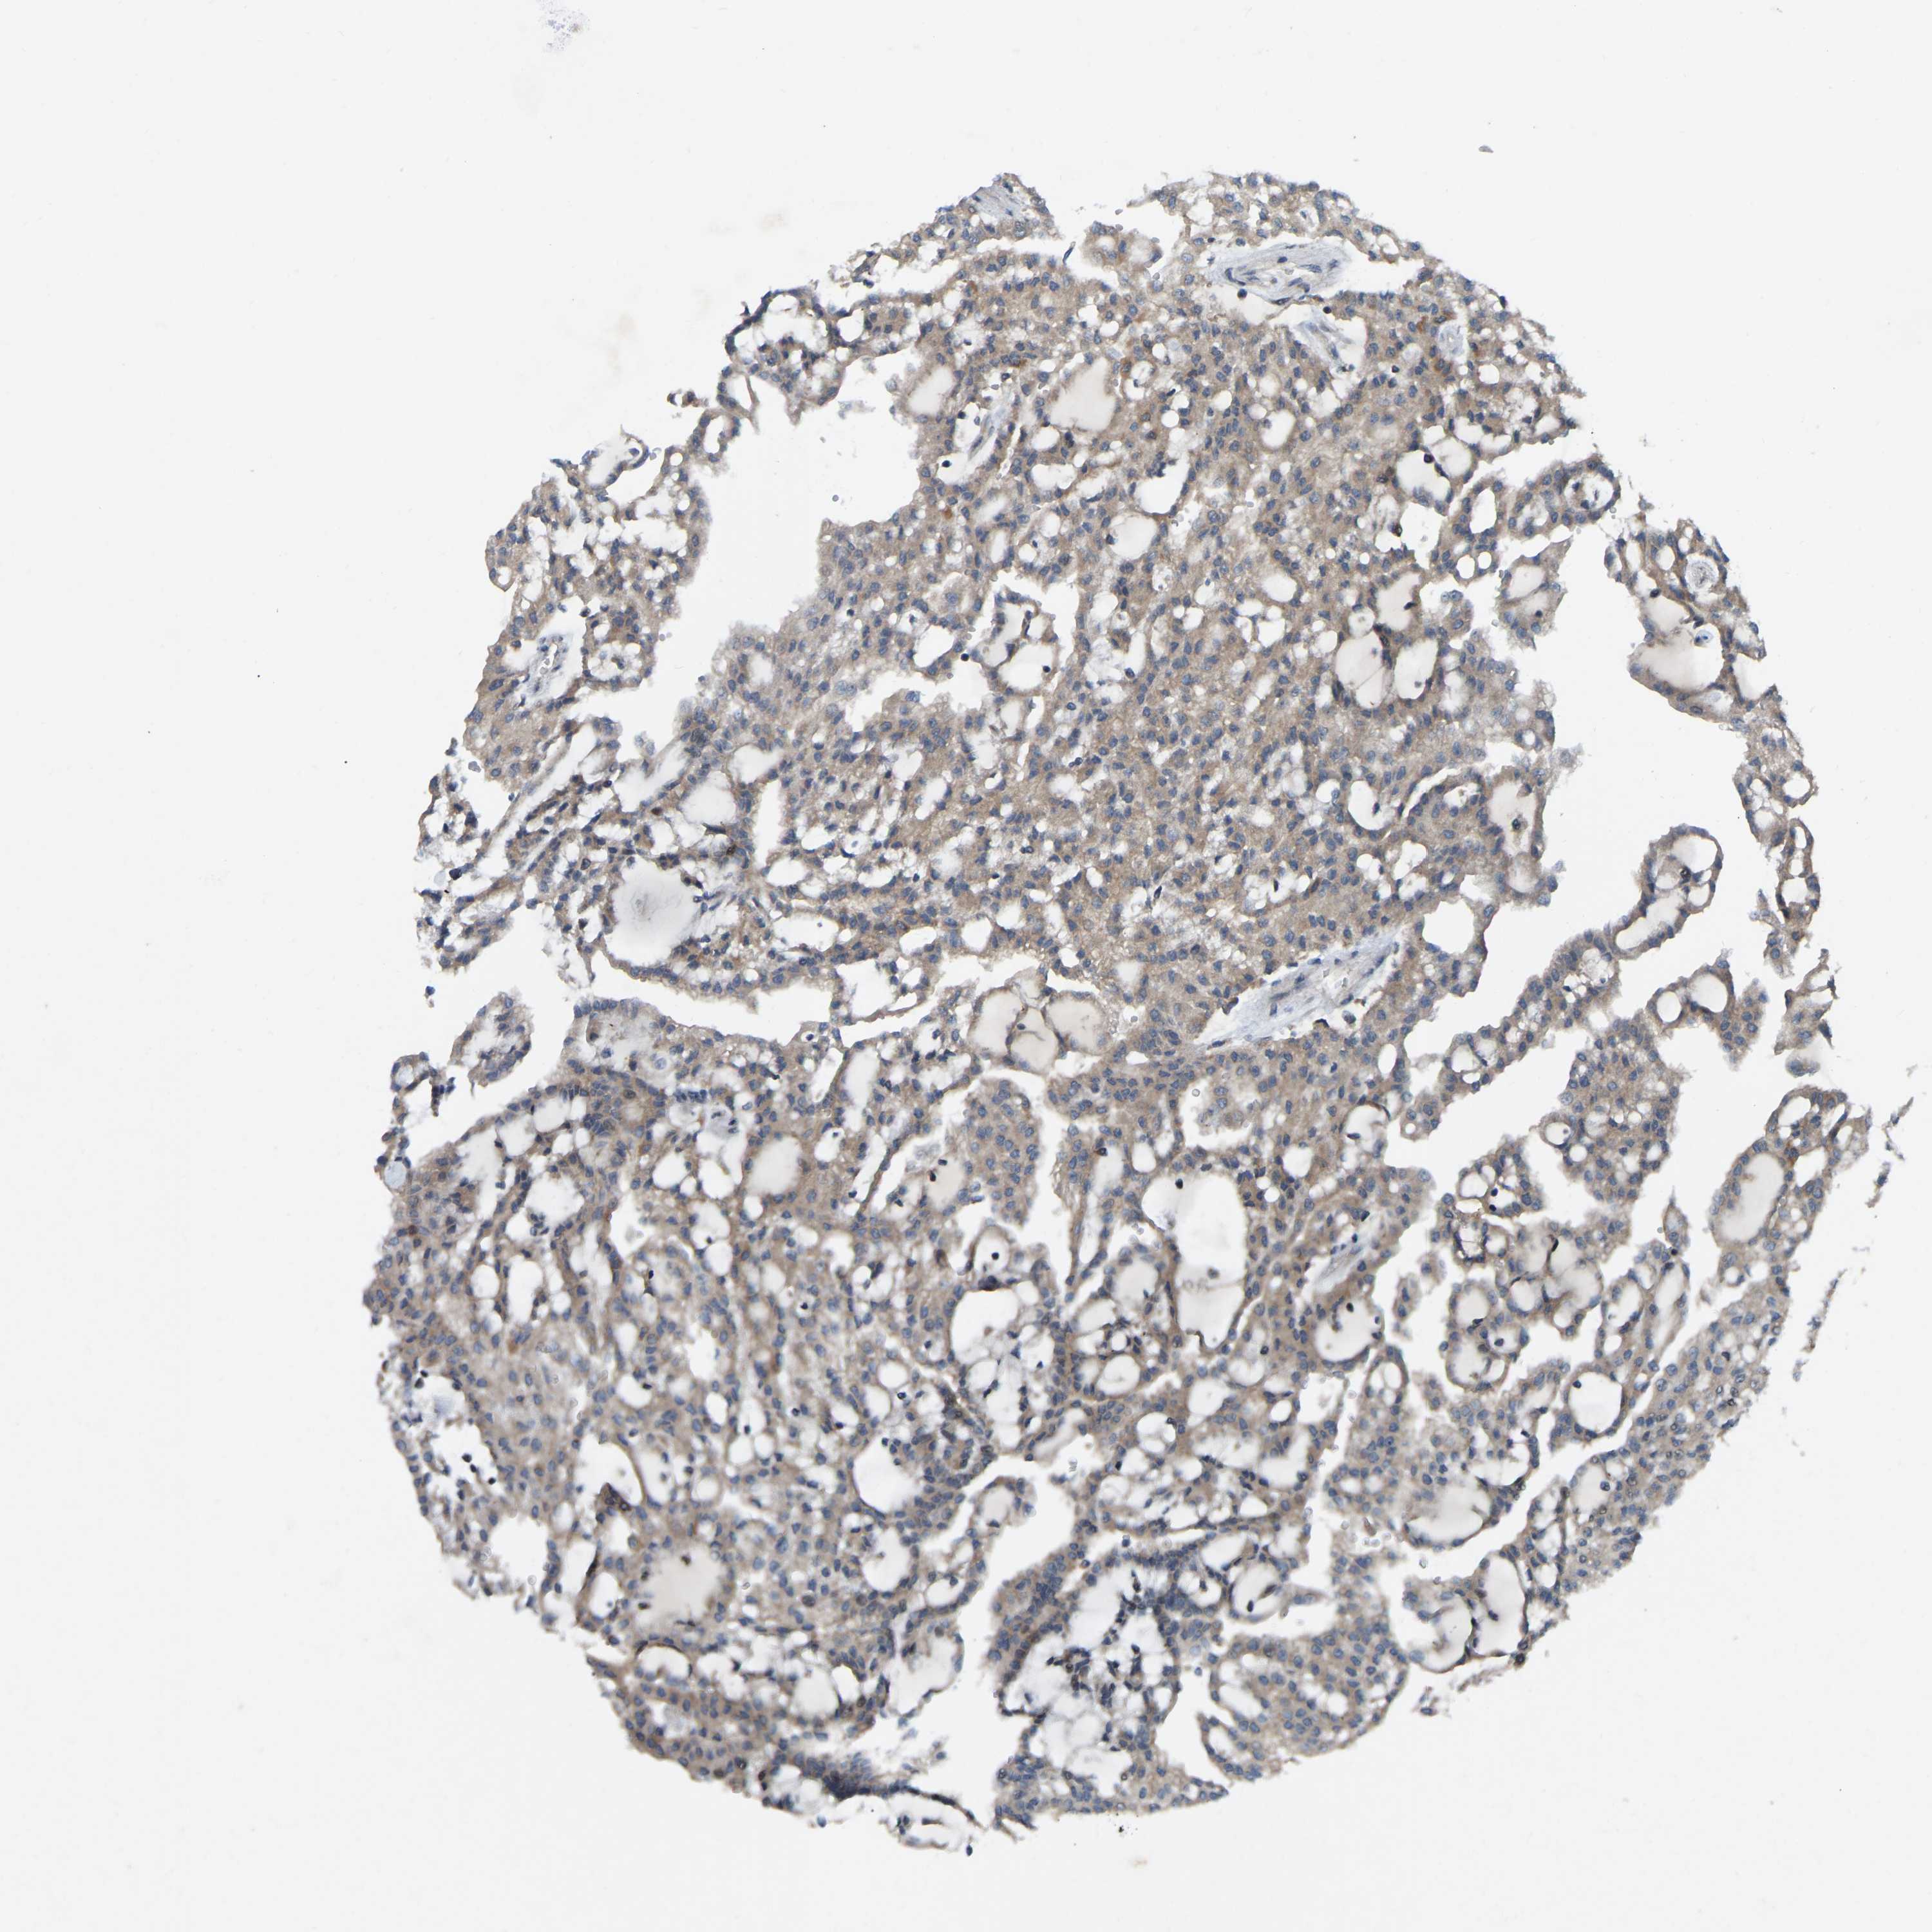

KIDNEY RENAL CLEAR CELL CARCINOMA (VALIDATION) - Interactive survival scatter ploti

The Survival Scatter plot shows the clinical status (i.e. dead or alive) for all individuals in the patient cohort, based on the same data that underlies the corresponding Kaplan-Meier plots. Patients that are alive at last time for follow-up are shown in blue and patients who have died during the study are shown in red.

The x-axis shows the expression levels (FPKM) of the investigated gene in the tumor tissue at the time of diagnosis. The y-axis shows the follow-up time after diagnosis (years). Both axes are complimented with kernel density curves demonstrating the data density over the axes. The top density plot shows the expression levels (FPKM) distribution among dead (red) and alive patients (blue). The right density plot shows the data density of the survived years of dead patients with high and low expression levels respectively, stratified using the cutoff indicated by the vertical dashed line through the Survival Scatter plot. This cutoff is automatically defined based on the FPKM cutoff that minimizes the p-score. The cutoff can be changed by dragging the vertical line or by entering a cutoff value in the square labeled "Current cut-off".

Under the Survival Scatter plot the p-score landscape (black curve; left axis) is shown together with dead median separation (red curve; right axis). Dead median separation is the difference in median mRNA expression between patients who have died with high and low expression, respectively. It is calculated as follows: median FPKM expression of dead patients with high expression - median FPKM expression of dead patients with low expression. This is intended to aid the user in visually exploring custom cutoffs and the associated p-scores and dead median separation.

Individual patient data is displayed and can be filtered by clicking on one or more of the category buttons on the top of the page. Categories describing expression level and patient information include: high, low, alive, dead, female, male and tumor stages. The scale of the x-axis can be toggled between linear and log-scale by clicking on the "x log" button. Mouse-over function shows TCGA ID, patient information and mRNA expression (FPKM) for each patient.

& Survival analysisi

Kaplan-Meier plots summarize results from analysis of correlation between mRNA expression level and patient survival. Patients were divided based on level of expression into one of the two groups "low" (under cut off) or "high" (over cut off). X-axis shows time for survival (years) and y-axis shows the probability of survival, where 1.0 corresponds to 100 percent.

PARL is not prognostic in Kidney Renal Clear Cell Carcinoma (validation)

Best expression cut offi

Based on the FPKM value of each gene, patients were classified into two groups and association between prognosis (survival) and gene expression (FPKM) was examined. The best expression cut-off refers the FPKM value that yields maximal difference with regard to survival between the two groups at the lowest log-rank P-value. Best expression cut-off was selected based on survival analysis .

When clicking on this number, the vertical dashed line indicating cut-off, the interactive survival plot, and the Kaplan-Meier curve will be adjusted to show results based on the best expression cut-off.

: 53.09

P scorei

Log-rank P value for Kaplan-Meier plot showing results from analysis of correlation between mRNA expression level and patient survival.

N/A

TCGA RNA samplesi

RNA-seq data is reported as average FPKM (number Fragments Per Kilobase of exon per Million reads), generated by the The Cancer Genome Atlas (TCGA) .

Normal distribution across the dataset is visualized with box plots, shown as median and 25th and 75th percentiles. Points are displayed as outliers if they are above or below 1.5 times the interquartile range. FPKM values of the individual samples are presented next to the box plot.

Average pTPM 56.5

Number of samples 100